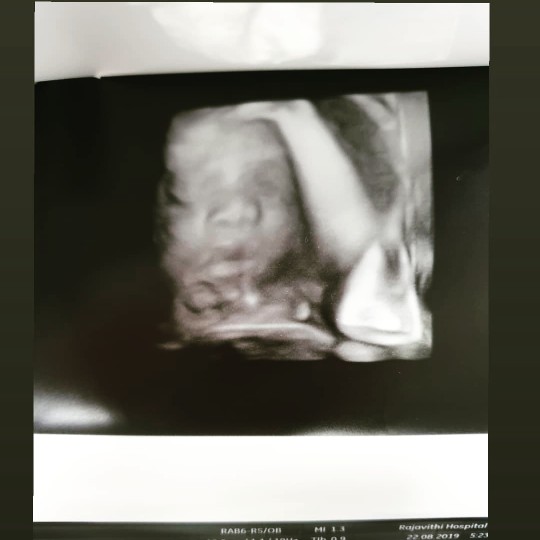

ลองไปซาวด์ดูนะคะ ชอบมากเลย ลูกชอบหลบหน้า บ้านนี้โรคจิตชอบไปซาวด์บ่อย

จับจังหวะนี้พอดีค่ะแม่ 🥰